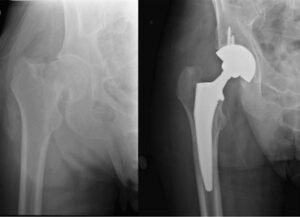

Patients with a hip fracture are at substantial risk for death, health complications, and reduced quality of life. Displaced sub capital and intracapsular femoral neck fractures unsuitable for reduction and primary fixation are usually treated with an arthroplasty procedure. Total Hip Arthroplasty (THA) offers improved functional outcomes and better health quotients in comparison to hemiarthroplasty (HA). THA may be cemented (CTHA) or uncemented (UTHA). The results of THA for acute fracture NOF were comparable to the results of THAs for other indications. The optimal treatment of mobile, independent patients who have sustained a displaced intracapsular fracture of the femoral neck remains controversial. Uncemented or cementless fixation of the femoral stem had been widely studied in comparison to the cemented fixation and outcomes have been found promising and equivalent. Displaced femoral neck fractures in elderly patients are typically treated with hemiarthroplasty (HA), however, rates of total hip arthroplasty (THA) are increasing for femoral neck fractures in the active elderly patients. The American Academy of Orthopaedic Surgeons and National Institute for Health and Care Excellence guidelines recommend total hip arthroplasty in all patients with displaced femoral neck fractures who are able to ambulate independently. In our centre, we do uncemented total hip arthroplasty for people below the age of 65years with quite good outcome.